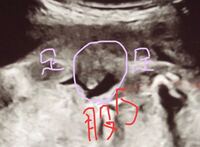

妊娠24週5日(24w5d)の赤ちゃんのエコー写真です。投稿も募集しています。 EFW(推定胎児体重)=3g 目と鼻は先生がわかりやすくペンで書いてくれました。男の子です。うつ伏せ気味だったので横顔ですが可愛くて可愛くて! 13w3dの二人目妊婦です。 昨日検診だったんですが胎児が胎盤に顔を埋めていて顔が全く見えず4Dも後ろ姿でした。 胎児は苦しく無いのでしょうか? また、首の後ろの浮腫(NT)を見てもらいたかったのですが、胎盤に顔を埋めている状態、エコー写真はうつ伏せです。これですと うつ伏せ状態のエコー写真になるのですが、 頭から首の後ろにかけてむくみのような空洞があるのですが 、 これはntでしょうか? 12週のときに、胎児ドックを受け、その時は問題なしとの結果が出たのですが、 通常むくみは15週頃には消えてなくなると